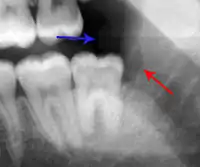

Lateral periodontal abscess (blue arrows) due to a fracture (green arrows)

A periodontal abscess (lateral abscess) is a collection of pus that forms in the gingival crevices, usually as a result of chronic periodontitis where the pockets are pathologically deepened greater than 3mm. A healthy gingival pocket will contain bacteria and some calculus kept in check by the immune system. As the pocket deepens, the balance is disrupted, and an acute inflammatory response results, forming pus. The debris and swelling then disrupt the normal flow of fluids into and out of the pocket, rapidly accelerating the inflammatory cycle. Larger pockets also have a greater likelihood of collecting food debris, creating additional sources of infection.[21]:443

Periodontal abscesses are less common than apical abscesses, but are still frequent. The key difference between the two is that the pulp of the tooth tends to be alive, and will respond normally to pulp tests. However, an untreated periodontal abscess may still cause the pulp to die if it reaches the tooth apex in a periodontic-endodontic lesion. A periodontal abscess can occur as the result of tooth fracture, food packing into a periodontal pocket (with poorly shaped fillings), calculus build-up, and lowered immune responses (such as in diabetes). Periodontal abscess can also occur after periodontal scaling, which causes the gums to tighten around the teeth and trap debris in the pocket.[21]:444–445 Toothache caused by a periodontal abscess is generally deep and throbbing. The oral mucosa covering an early periodontal abscess appears erythematous (red), swollen, shiny, and painful to touch.[22]